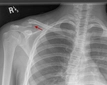

Bu belirtiler acil müdahale gerektiren durumlar arasında yer alır ve dikkatle değerlendirilmelidir. Tanı YöntemleriKalça kırığını teşhis etmek için çeşitli tanı yöntemleri kullanılmaktadır. Bunlar arasında:

Bu yöntemler, kalça kırığının tam yerini ve türünü belirlemek için kritik öneme sahiptir. Tedavi YöntemleriKalça kırığının tedavisi, kırığın tipi, hastanın yaşı ve genel sağlık durumu gibi faktörlere bağlı olarak değişiklik gösterir. Genel olarak kullanılan tedavi yöntemleri şunlardır: